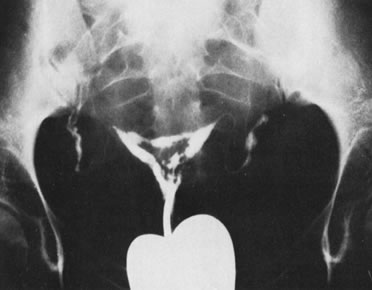

Although a hysterosalpingogram is perhaps the most accurate screening method to detect this condition, the distortion seen on the hysterosalpingogram may on many occasions not accurately represent the true condition; visual appraisal of the uterine cavity is most valuable for ascertaining the presence of adhesions and their extent, quality, and components and at the same time providing their direct treatment by division under hysteroscopic guidance. Depending on the extent of adhesions to be divided, hysteroscopic lysis, with or without concomitant laparoscopy, is the preferred method of surgically dividing intrauterine adhesions.

The extent of the occlusion, and the type of adhesions involved, is predictive of the outcome in these patients (Figs. 29, 30, and 31).

Fig. 29. Hysterosalpingogram shows intrauterine adhesions occluding a large portion of the uterine cavity.